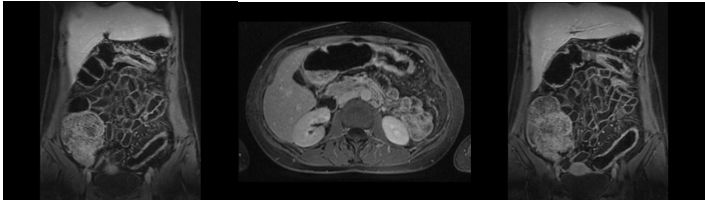

2013/7 byla referována na naše lůžkové oddělení pro relaps onemocnění - 10 řídkých stolic denně včetně nočních, křečovité bolesti břicha, subferbrilie. Před přijetím měla provedenou MR enterografii se známkami aktivity v rozsahu colon transversum, descendens a sigmoideum bez postižení tenkého střeva

MR 2013/6 MR obraz zánětu v rozsahu c. transversum, descendens a sigma, s opacifikací stěny po aplikaci KL, tzn. se známkami aktivity.